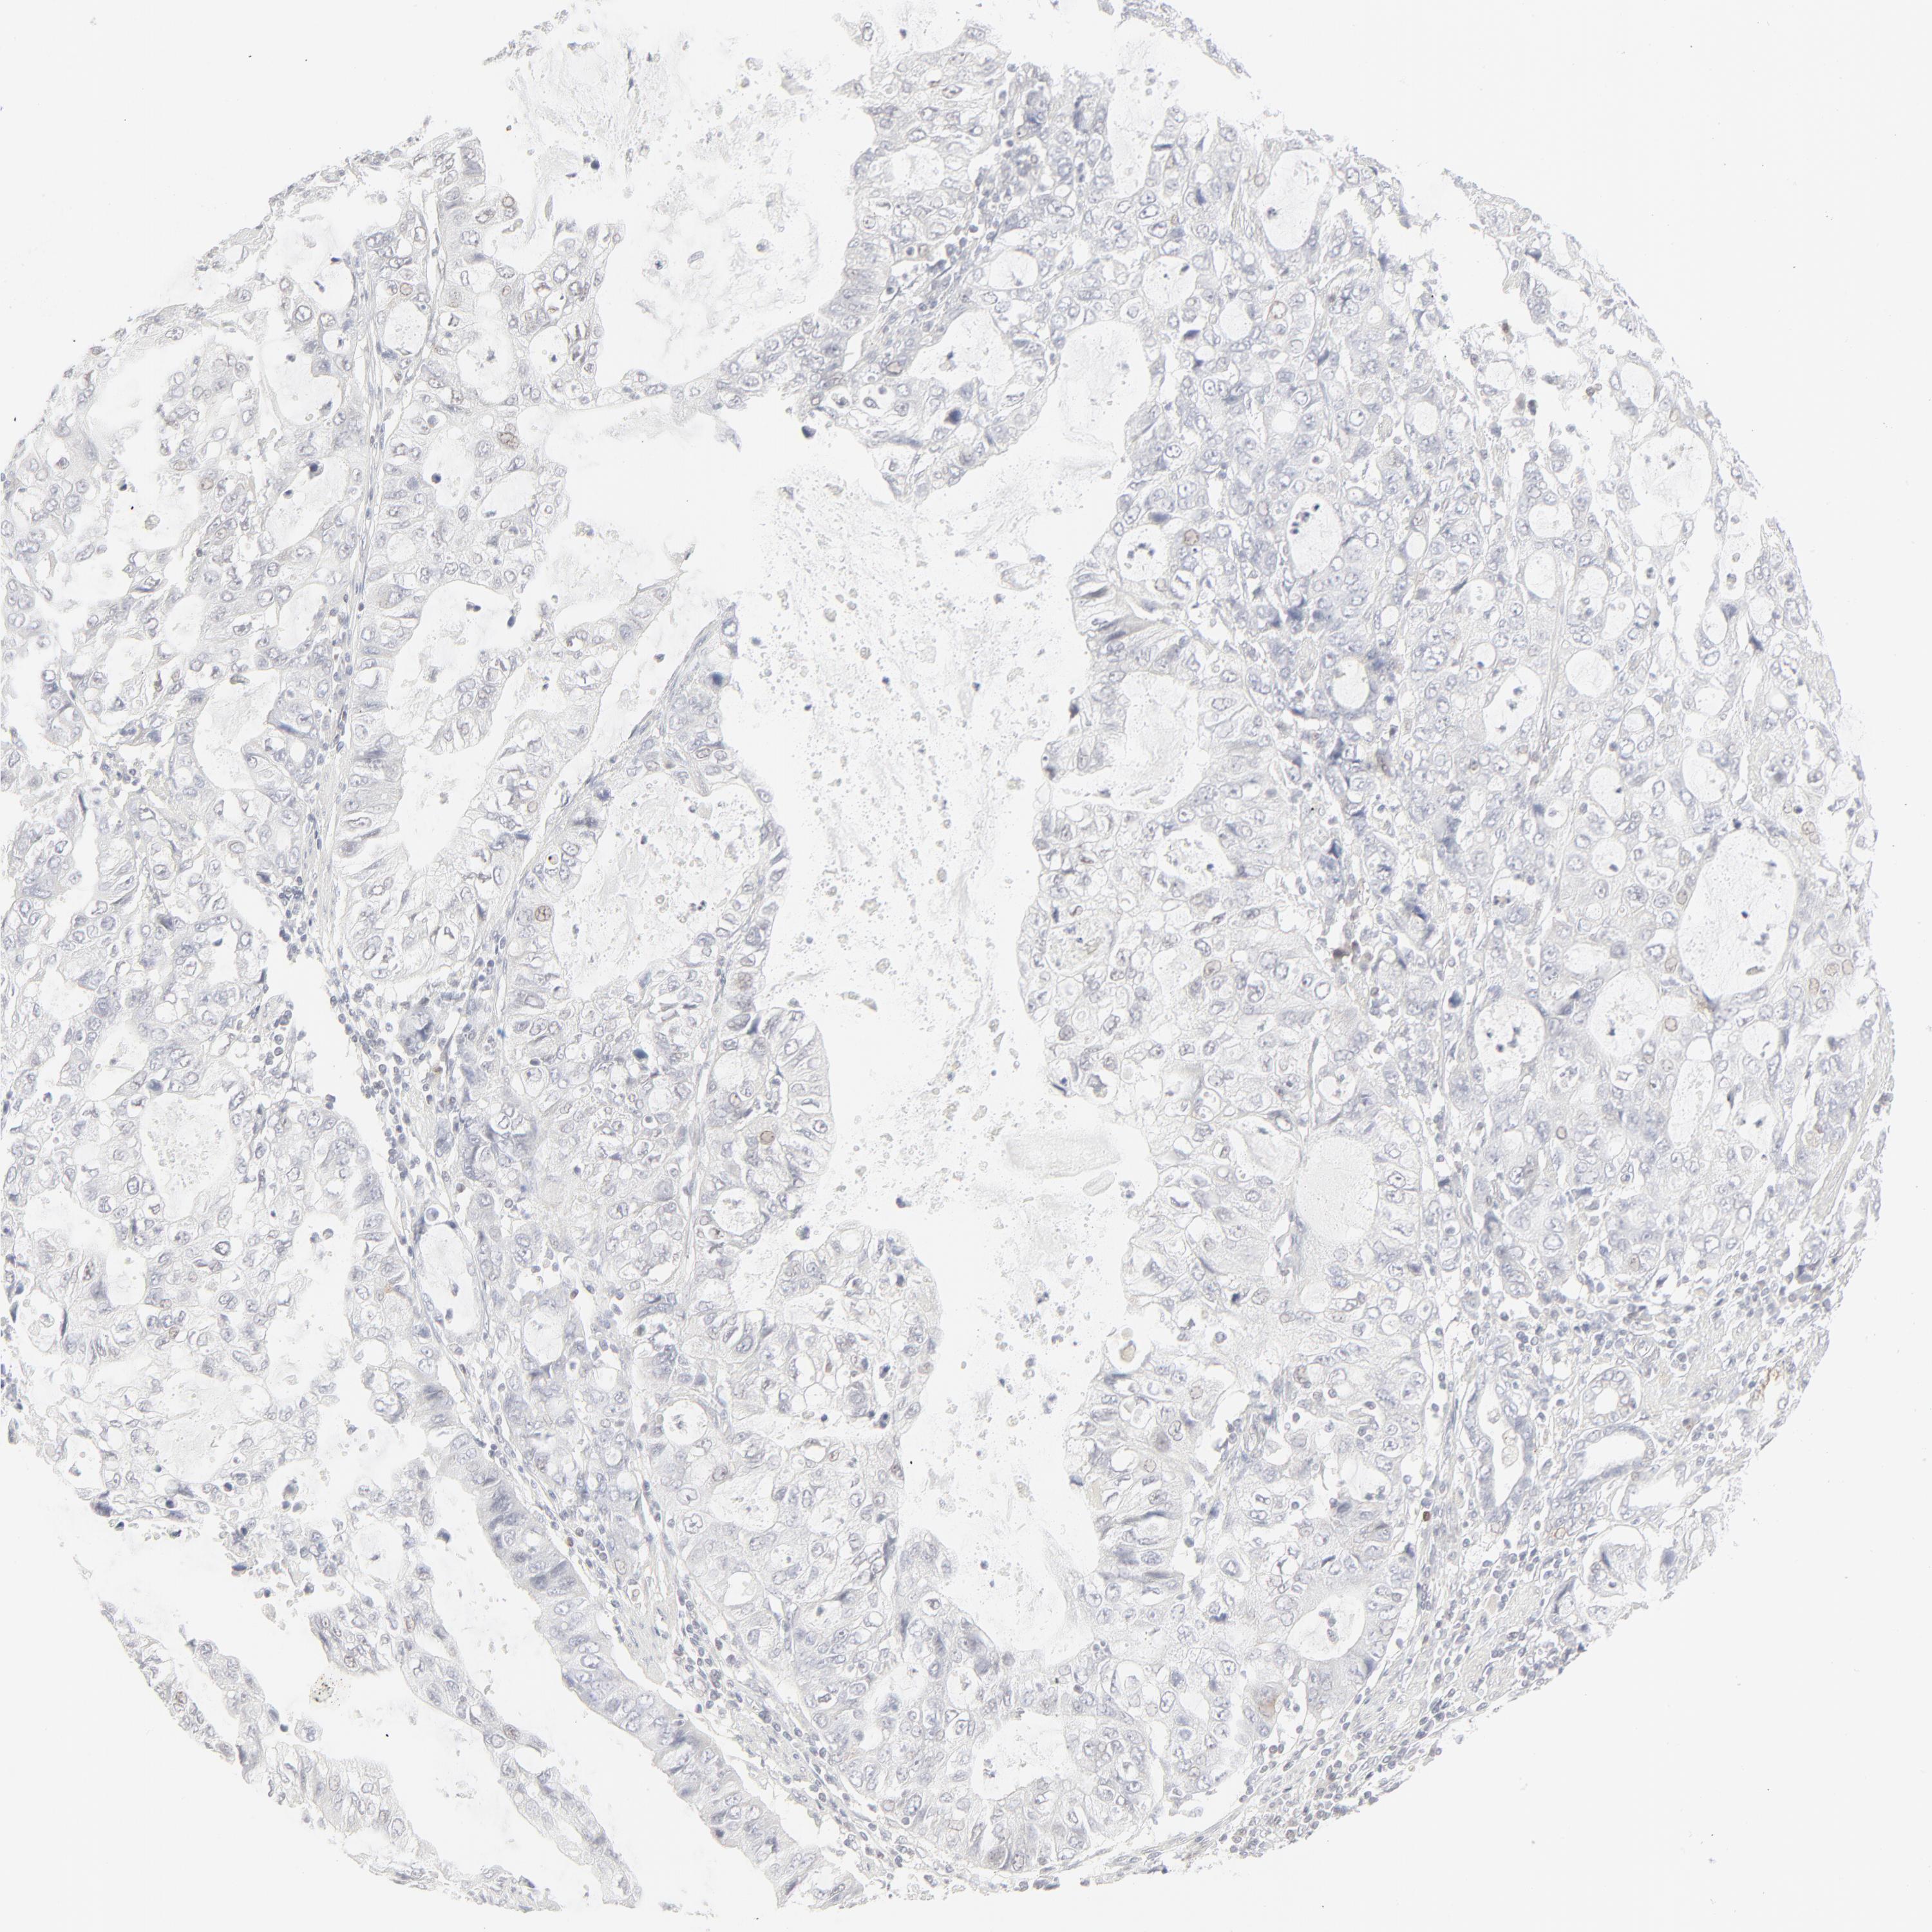

STOMACH CANCER - Protein expressioni

A mouse-over function shows sample information and annotation data. Click on an image to view it in a full screen mode. Samples can be filtered based on level of antibody staining by selecting one or several of the following categories: high, medium, low and not detected. The assay and annotation is described here.

Note that samples used for immunohistochemistry by the Human Protein Atlas do not correspond to samples in the TCGA dataset.

Antibody stainingi

Antibody staining in the annotated cell types in the current human tissue is reported as not detected, low, medium, or high, based on conventional immunohistochemistry profiling in selected tissues. This score is based on the combination of the staining intensity and fraction of stained cells.

Each image is clickable and will lead to virtual microscopy that enables deeper exploration of all samples and also displays staining intensity scores, fraction scores and subcellular localization as well as patient and tissue information for each sample.

Antibody HPA048321

Antibody CAB003843

Staining

High

Medium

Low

Not detected

Intensity

Strong

Moderate

Weak

Negative

Quantity

>75%

75%-25%

<25%

None

Location

Nuclear

Cytoplasmic/membranous

Cytoplasmic/membranous,nuclear

Adenocarcinoma, NOS